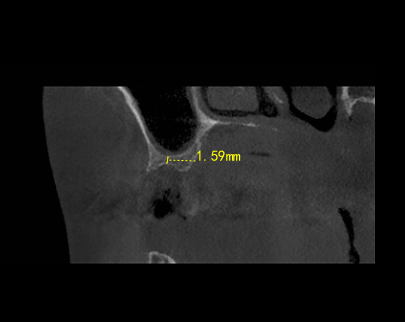

口腔CT片更直观地暴露了问题:支撑牙齿的骨头(牙槽骨)几乎被“啃”掉了三分之二,最薄的地方仅1.59mm......

患者术前牙槽骨最“薄”处仅1.59mm

时间来到了2025年5月,但CT片显示倪女士16号牙的骨量只有1.59mm太少了,这远远还达不到做种植牙的条件!